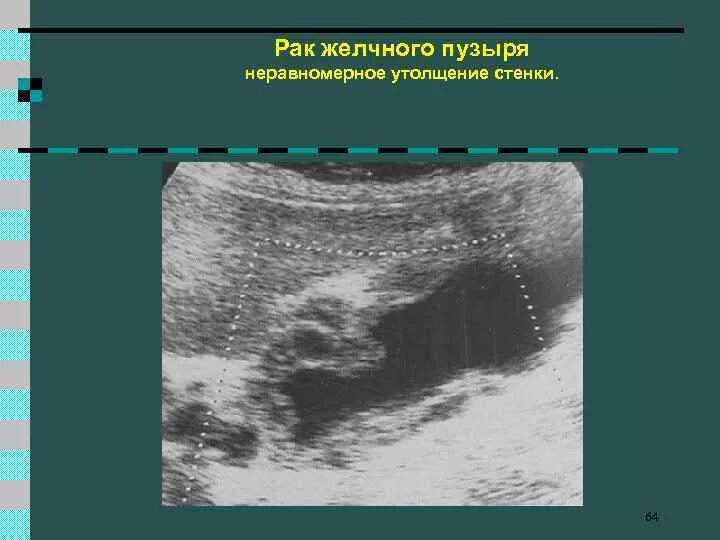

Метастазы в желчном